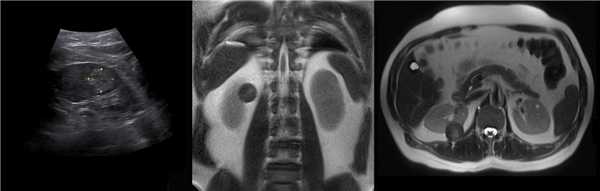

Рисунок. У новорожденного на УЗИ почек определяется гидронефроз (1) и расширенный мочеточник (2) справа. В мочевом пузыре двустороннее уретероцеле (3). При исследовании левой почки структурных изменений не выявлено.

Рисунок. На УЗИ определяется удвоенная чашечно-лоханочная система, расширена лоханка верхнего сегмента (1) и мочеточник на всем протяжение (2, 3), в мочевом пузыре уретроцеле (4). Полное или неполное удвоение чашечно-лоханочной системы возможно увидеть с помощью КТ-урографии.

Рисунок. Двустороннее уретероцеле на УЗИ: в режиме ЦДК из верхушек уретероцеле определяется выброс мочи.

Рисунок. На УЗИ в уретероцеле определяется гиперэхогенная структура с акустической тенью — камень. Уретероцеле может являться одним из факторов, способствующих камнеообразованию.